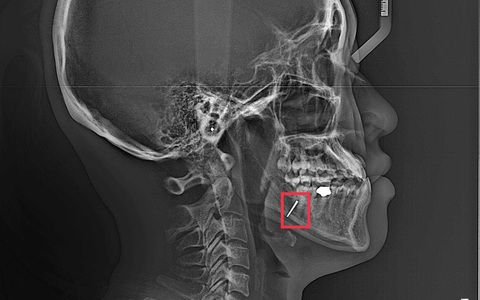

Sau đó, bà L. đến Bệnh viện Đa khoa tỉnh Phú Thọ thăm khám. Tại đây, sau khi thăm khám, xét nghiệm máu tổng quát, chụp cắt lớp vi tính vùng hàm mặt, bà L. được chẩn đoán viêm hoại tử xương hàm dưới bên trái trên nền bệnh đái tháo đường. Tại vị trí răng đã nhổ, các bác sĩ phát hiện vẫn còn mảnh chân răng chưa được lấy hết.

Bà L. được chỉ định phẫu thuật nạo vét ổ viêm, lấy mảnh xương chết. Sau phẫu thuật 5 ngày, bà L. gần như hồi phục hoàn toàn, không còn đau nhức, không còn sưng, viêm và được ra viện.